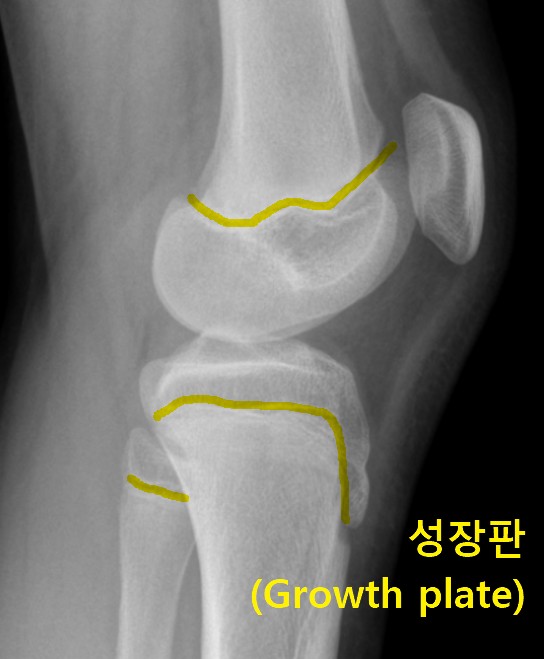

X-ray 사진을 찍어보면, 검게 보이던 성장판이 사라지고 뼈가 하나로 붙은 것처럼 보입니다. 왼쪽의 사진은 실제 제 아이의X-ray 사진입니다. 빨간색 네모 부분이 성장판입니다. 공간이 벌어져있고 얇은 판 같은 금이 보입니다. 하지만 그 옆의 사진은 뼈가 하나로 길게 연결되어 있습니다. 이렇듯 성장판이 모두 뼈로 바뀌고 더 이상 뼈 양 끝에 물렁한 연골이 사라지면 이를두고 '성장판이 닫혔다'고 표현합니다.